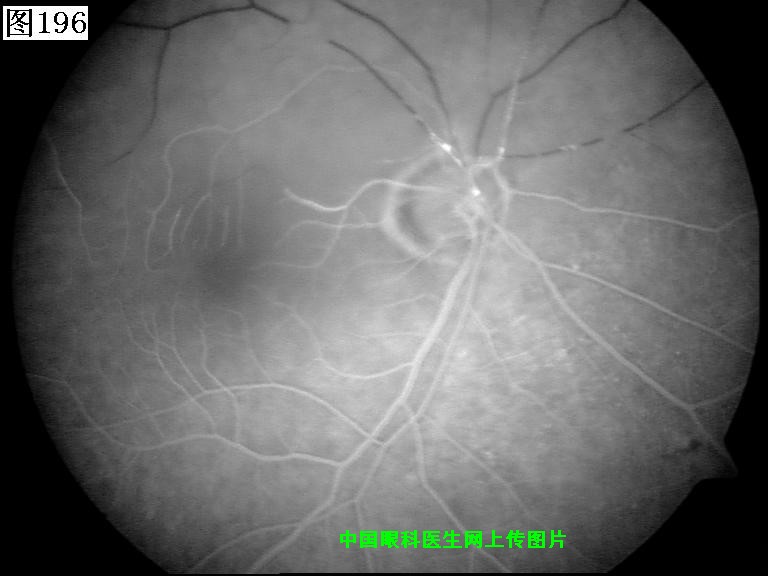

193 194 195 196